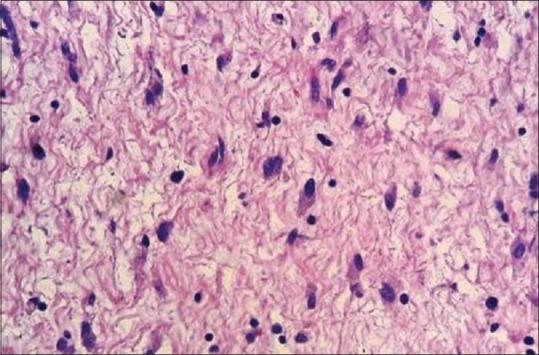

The angiomyxomas are rarely reported in the head and neck region; this paper entails a case of aggressive angiomyxoma presenting as a growth in the maxillary anterior alveolar mucosa and lip region for 1 year, which was accurately identified and treated successfully by surgical excision. An attempt has been made to highlight the clinical and pathologic stand out features of this tumor with intricate emphasis, alongside a literary review.

血管黏液瘤在头颈部区域鲜有报道;本文报道了1例侵袭性血管黏液瘤,该肿瘤表现为上颌前牙槽黏膜和唇部肿物,病程1年,经手术切除得以准确诊断并成功治疗。本文在进行文献回顾的同时,着重强调了该肿瘤的临床和病理突出特征。